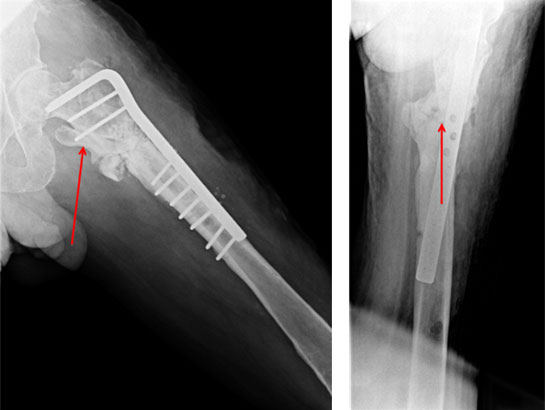

This 67 year gentleman had a fall at home in 2006. He had a subtrochanteric fracture (below hip joint) of left femur. He was operated and fixation was done using an intra-medullary nail.

2006

Unfortunately he developed infection and was re-operated during which an external fixator was applied to clear out the infection.